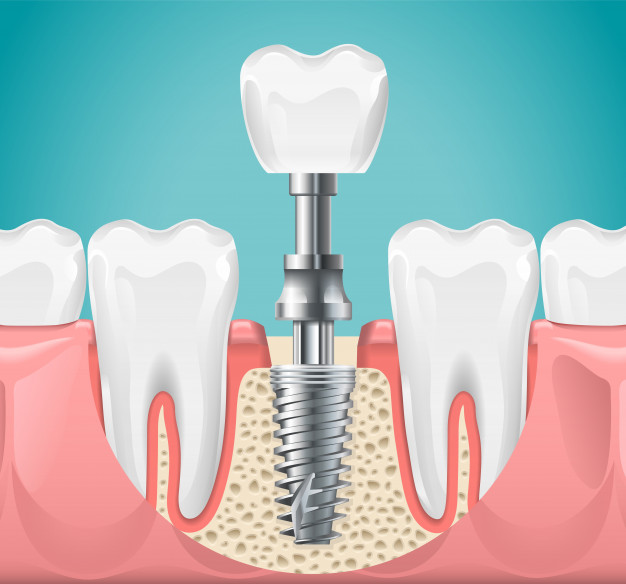

做種植牙的危害:

1、流血。

種植牙齒是一種消融手術,通常情況下種完牙後,應該是沒有流血的。

假如流血應該是種植牙齒醫師的種植牙齒的技術性,不合格而致的。

因種植牙齒對牙骨質或是有一定的損害的,假如牙科醫生在粘骨膜脫離時影響大或黏膜下脫離普遍,尤其是手術後擠壓欠佳,均易産生黏膜下或皮下出血。

2、創口開裂。

種植牙齒病人會發生這樣的事情,是由于在種植牙齒的情況下,手術縫合太緊或太松而致使的。

特別是在在種植牙齒清理不合理,引起感柒的情形下,更易造成部分創口開裂。

處理種植牙的危害的辦法是,立即創面,再度手術縫合,才可以防止牙齒種植體曝露。

做種植牙的優點:

1、種植牙齒

比其余的修補法更舒服,更便捷。

種植牙齒不應用活動假牙必不可少的基托與卡簧,沒有不適感,十分舒服、便捷,並且有助于維持口腔科的日常保潔。

2、使用方便,種植牙手術是一個較小的牙槽手術,相近拔牙齒,選用局麻,外傷小,手術後就可以進餐,幾乎低疼痛。

因爲采用的是與身體相溶性很好的生物技術,種植牙齒對身體不造成傷害。

3、合理維護牙槽,種植牙齒對整體牙槽具有不錯的保障功效,人的牙齒和樹木一樣,大樹固步自封才可以花繁葉茂,牙齒缺損後牙槽如同土壤侵蝕,牙槽會産生差異水平的廢用性衰老和消化吸收。

種植牙齒的人造牙龈深植于牙槽中,因而能有效的預防牙槽骨萎縮和牙槽骨吸收。